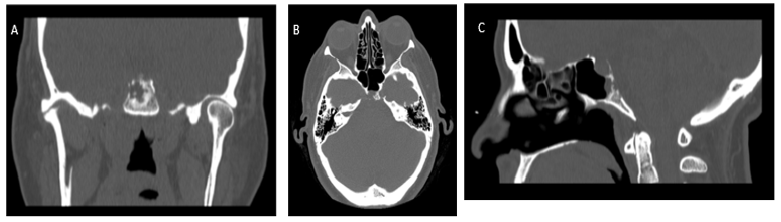

I present the case of a 52-year-old patient who, after a nasal swab sampling for SARS-CoV-2 diagnosis, presented CSF fistula. After the swab, she reported a burning sensation and nasal leak of the left nostril after 24 hours, persistent and intermittent when she bended the head down and with certain head movements. Liquid was collected for several days, and the B-trace levels were in the upper reference limit. A brain MRI revealed a lesion on the clivus with extension towards the sphenoid sinus and the posterior cranial fossa that suggested ecchordosis physaliphora, with noticeable secondary CSF leakage with liquid on the dependent portion of the sphenoid sinus [1-6].

Results

The lesion of the clivus was excised and an endonasal endoscopic closure of the dural defect was performed through the fascia lata, fat, and Hadad flap. 3 days after discharge, she presented an emetic event with a new episode of CSF rhinorrhea. An emergency repair of the fistula was successfully conducted. Finally, the histological results revealed salivary gland heterotopia [7-13] (Figures 1-3).